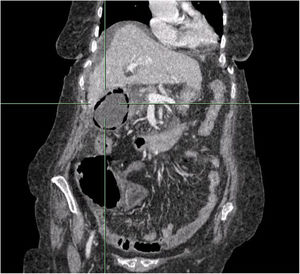

La TC abdominal con contraste muestra áreas en vidrio esmerilado bilaterales, periféricas, basales pulmonares, sugestivas de SARS-CoV-2 con PCR negativa. Vesícula biliar distendida con paredes llenas de aire y con barro biliar con líquido perihepático y pélvico (fig. 1).

Se (fig. 2) descarta cirugía por elevada morbimortalidad, consensuando tratamiento conservador con antibióticos. Exitus a las 24 h del ingreso.

Diagnóstico: colecistitis enfisematosa.